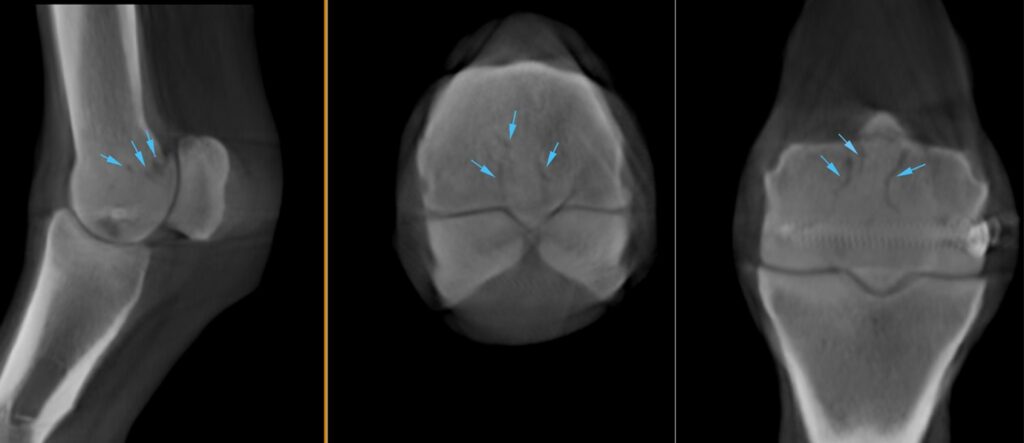

CT findings

With a fetlock fracture suspected, the horse underwent a scan using Hallmarq’s Vision CT machine. This revealed several hypoattenuating lines entering the palmar metacarpus at the level of the physeal scar abaxial to the proximal aspect of the sagittal ridge of the third metacarpus that likely represented a course of blood vessels (Figure 2).